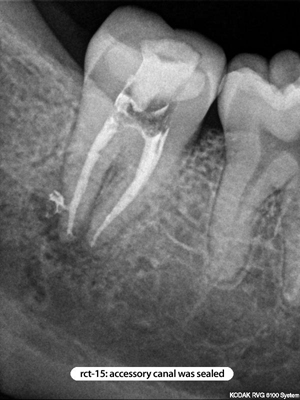

Root Canal Cases